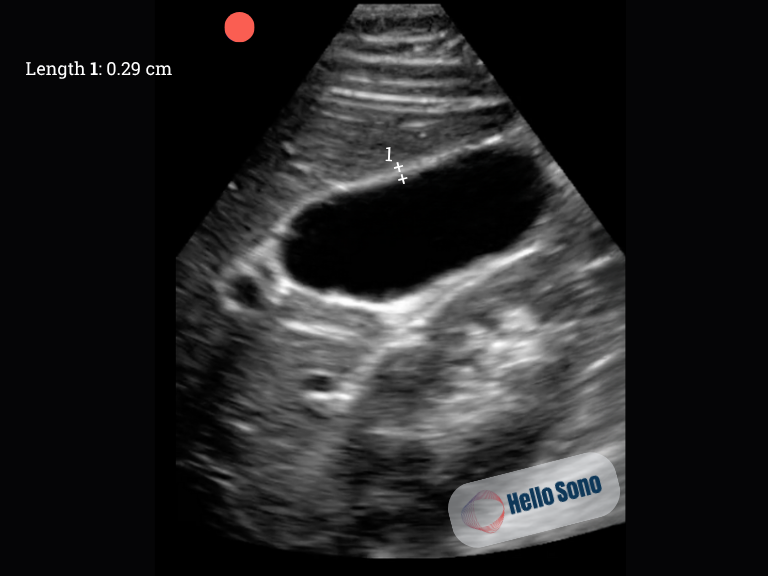

A representative image is shown below (Image 1). The patient does not exhibit a sonographic Murphy’s sign.

In a normal right upper quadrant ultrasound (Image 2), the gallbladder appears as an anechoic (black), pear-shaped structure with thin, smooth walls. There are no echogenic foci or posterior shadowing within the lumen. The CBD is typically less than 6 mm in diameter in patients under age 70. The anterior gallbladder wall measures less than 3 mm.

Ultrasound image of the normal gallbladder in the long plane. Length 1corresponds to the anterior gallbladder wall diameter (AGWD). The gallbladder lumen is free of internal echoes.

Image 2: Ultrasound image of the normal gallbladder in the long plane. Length 1corresponds to the anterior gallbladder wall diameter (AGWD). The gallbladder lumen is free of internal echoes.